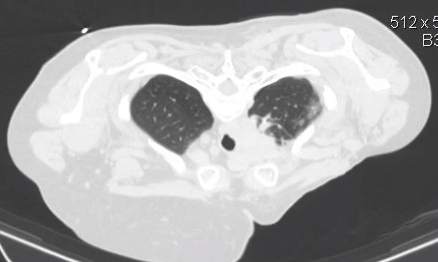

控制性气胸诱发肺塌陷是解决经肺纵膈活检的方案之一。人工气胸技术包括超声或透视引导,CT引导下置6F导管于胸膜腔内,由CT监视下注射600-1600ml 空气产生肺塌陷,活检后经导管再将空气抽出,拔管。

气胸气体抽出后的CT